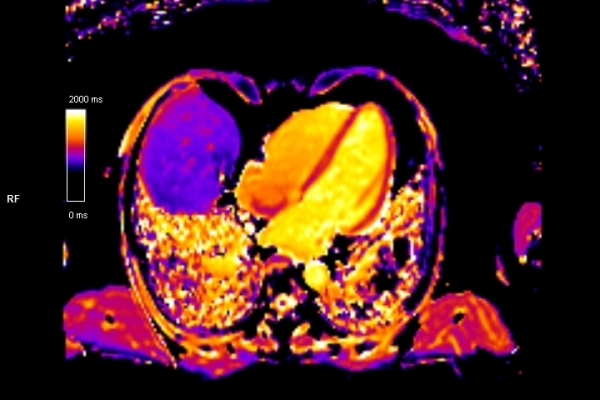

Detailbild MRT

Modernste Bildgebung für jeden Bereich Ihres Körpers

Entdecken Sie, welche CT- und MRT-Untersuchungen in unserer Radiologie für jeden Bereich Ihres Körpers möglich sind.

• Kardiovaskuläre Bildgebung (MRT- und CT-Untersuchungen des Herzen)

Was ist der Unterschied zwischen einer MRT- und einer CT-Untersuchung?

Die MRT (Magnetresonanztomographie) arbeitet mit Magnetfeldern und Radiowellen und eignet sich besonders für Untersuchungen der Weichteile wie Gehirn, Muskeln oder Gelenke. Die CT (Computertomographie) nutzt Röntgenstrahlen und liefert schnelle, hochauflösende Bilder, insbesondere für Knochen, Lunge oder innere Organe. Die Wahl der jeweiligen Untersuchung richtet sich an das individuelle Krankheitsbild und wird bei der Überweisung festgelegt.